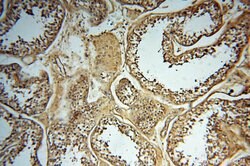

SYK Rabbit anti-Human, Mouse, Rat, Polyclonal, Proteintech

This gene encodes a member of the family of non-receptor type Tyr protein kinases. This protein is widely expressed in hematopoietic cells and is involved in coupling activated immunoreceptors to downstream signaling events that mediate diverse cellular responses, including proliferation, differentiation, and phagocytosis. It is thought to be a modulator of epithelial cell growth and a potential tumor suppressor in human breast carcinomas. Alternatively spliced transcript variants encoding different isoforms have been found for this gene.Specifications

| Immunohistochemistry (Paraffin) | |

| Human, Mouse, Rat | |